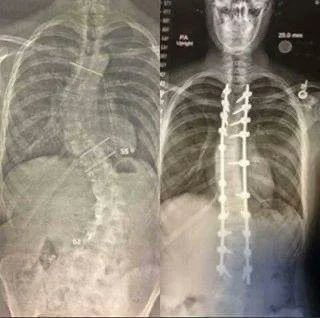

8. X-ray of a person's back before and after scoliosis surgery. The operation lasted 14 hours. Surgeons drilled metal rods into the spine. Image